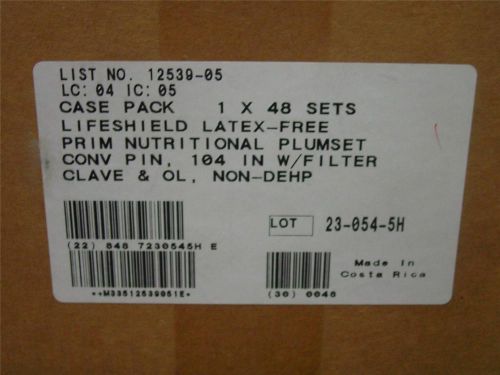

1 case 48 qty Primary I.V. PlumSet , Convertible Pin, 104 Inch 12539-05 plum